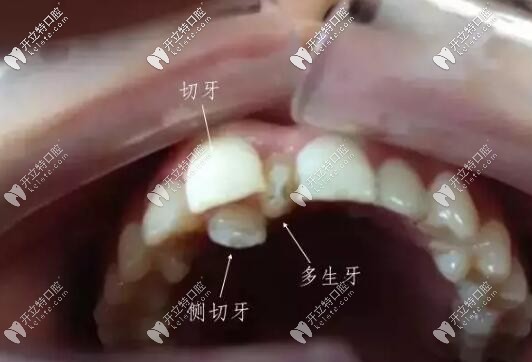

萌出的多生牙

智齒和多生牙并不是一個(gè)概念。多生牙從形態(tài)、牙根的數(shù)量,均不同于正常牙。

兒童:多生牙一般是在兒童換牙時(shí)長出,容易導(dǎo)致恒牙不能順利萌出。即使萌出,也會(huì)因排列不齊、擁擠不堪、容易藏食物殘?jiān)?,給齲齒、牙髓炎的發(fā)生創(chuàng)造了條件,所以大部分需要拔除。

1、如果多生牙形態(tài)異常,導(dǎo)致門牙中間有縫,或者占據(jù)牙列空間,使得別的牙齒擁擠或者覆蓋增大,需要拔除。